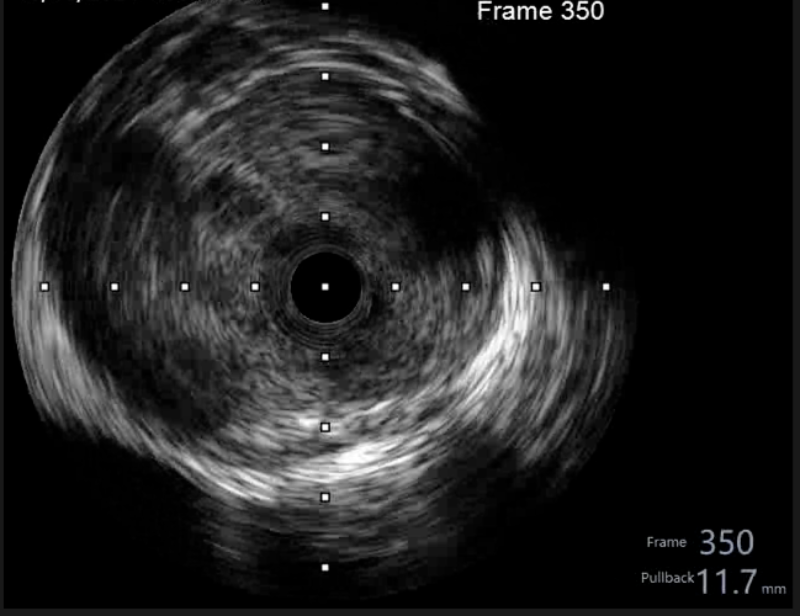

在惠州市中心人民醫(yī)院派駐博羅分院專家、博羅分院心血管內(nèi)科謝桂庭主任和謝志恒科副主任的帶領下,成功開展了博羅分院第一例冠狀動脈血管內(nèi)超聲(IVUS)檢查。術中行冠狀動脈血管內(nèi)超聲(IVUS)檢查:回旋支中段瘤樣擴張,少量血栓影,最大管腔直徑約6mm,未見夾層、血腫(圖4、5)。患者病變?yōu)楣诿}瘤樣擴張并血栓形成,予抗栓等治療后患者好轉(zhuǎn)出院。

文章配圖

(圖4)